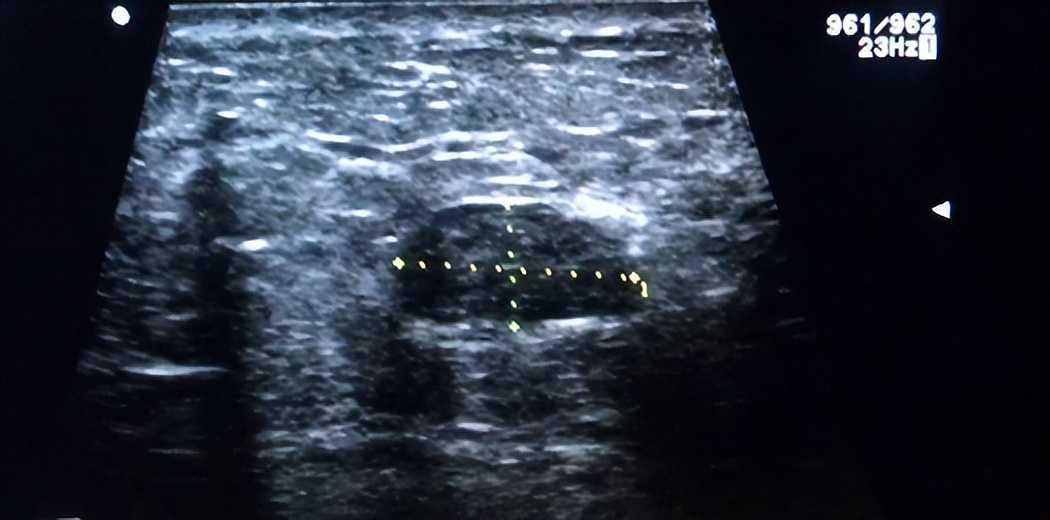

陈敏原以为只是一时的急火攻心,可没想到之后这股胀痛反反复复地出现,连月经都结束了还没有消失。陈敏觉得不对劲,便去医院做了个检查,结果查出她的右侧乳房内长了一个5mm左右的结节。陈敏忙问医生需不需要做手术,医生摇了摇头向她解释道:“从影像上来看,你的结节边界清楚、没有血流信号,且BI-RADS分类为3级,说明是良性结节,只需要定期复查就好了,平时一定要注意注意休息、调整情绪。”

乳腺超声提示,陈敏右侧乳房内的结节已经增大到了2cm,且边界不清、形态不规则,内部回声不均匀,边缘可见大量血流信号,BI-RADS分级为5级。5级的结节大概率为恶性,但需要穿刺活检确认。3天之后,病理结果出炉,确诊陈敏的确患上了乳腺癌。